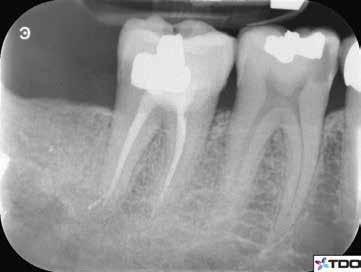

6. a–d. ábrák: A bal alsó második nagyőrlőfogon (3.7) kialakított konzervatív hozzáférési nyíláson keresztül végzett endodonciai kezelés lépései. A mezialis gyökér jelentős mértékben görbült. A gyökértömés hidraulikus kondenzációs technikával készült.

b. ábrák: A jobb alsó első nagyőrlőfogon (4.6) lévő cirkóniumkoronán keresztül elvégzett endodonciai kezelés. A hozzáférési nyílás kialakítása a lehető legkonzervatívabb módon történt. A gyökértömés hidraulikus kondenzációs technikával készült.

egyszerű obturációs technika, az anyag viszkozitási tulajdonságai és a pulpakamra viszonylag egyszerű tisztíthatósága a kezelésünk prognózisának veszélyeztetése nélkül teszi lehetővé az endodonciai beavatkozások lehető legkonzervatívabb módon történő kivitelezését. A bemutatott esetek ellátása során az Aurum Blue rendszert (Meta Biomed) használtuk a gyökércsatornák megmunkálására, míg a gyökértömés elkészítése során hideg hidraulikus kondenzációs technikát alkalmaztunk a kalcium-szilikát alapú CeraSeal (Meta Biomed) sealer felhasználásával (8. ábra).

Esetbemutatás (2., 3.)

Mindkét esetben irreverzibilis pulpitis miatt vált szükségessé a fogak endodonciai kezelése (6. a-d. és 7. a-b. ábrák). Az esetek ellátása során mindvégig minimálinvazív megközelítést alkalmaztunk. A hozzáférési nyílás kialakításától kezdve az endodonciai kezelés befejezését követő csonkfelépítésig, minden beavatkozás ennek megfelelően történt.

A konzervatív módon kialakított hozzáférési nyíláson keresztüli végzett kezelések során az egyik legnagyobb kihívást a gyökértömés elkészítése jelenti. Az egyenes irányú hozzáférés hiánya, a korlátozott rálátás és a pulpakamra kisméretű hozzáférési nyílása miatt csökkent hatékonyságú tisztíthatósága mind olyan faktorok, amelyeket figyelembe kell venni, ha minimálinvazív hozzáférést alakítunk ki.15 A kalcium-szilikát alapú sealerek fizikai tulajdonságai lehetővé teszik a klinikusok számára, hogy leküzdjék ezeket az akadályokat. A viszonylag